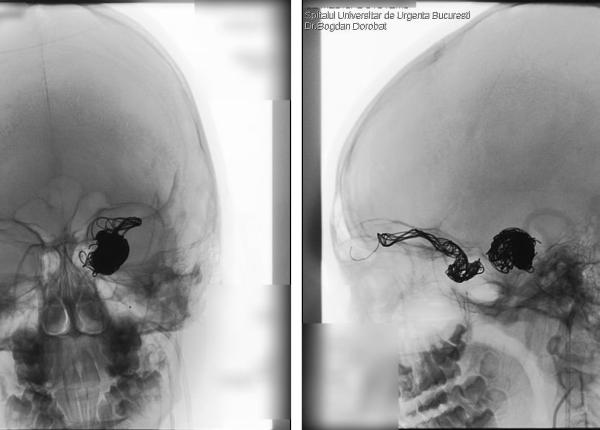

Angiografia, procedura de vizualizare a venelor. Identifică zonele blocate din vasele de sânge și depistează anevrismele

Angiografia identifică venele blocate și depistarea unui anevrism.